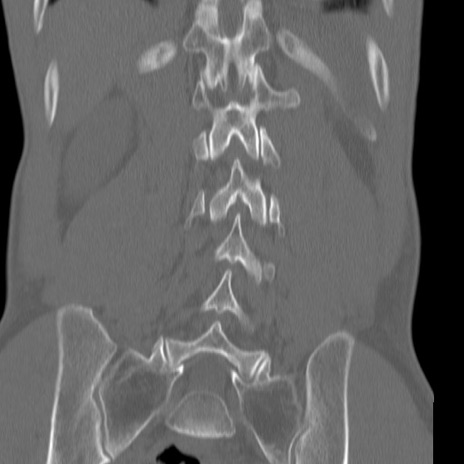

症例3 腰椎CT(冠状断像)

腰椎CT

矢状断像